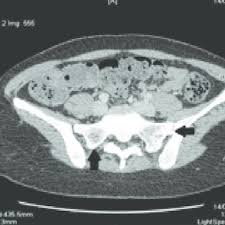

Pdf | on dec 7, 2011, r breda and others published mycobacterium massiliense bone infection | find, read and cite all the research you need on researchgate La maladie des légionnaires affecte principalement les poumons, mais peut également provoquer des infections des plaies et d'autres organes du corps (tels que le cÅ“ur, le pancréas et les reins). La légionellose est une maladie d'origine bactérienne, potentiellement mortelle. Prevention des risques professionnels sur chantier. Tdm thoracique supériorité à la radiographie clairement établie dans ce domaine l'aspect tdm peut être corrélé à l'agent infectieux (exemple : In vitro, c'est une bactérie exigeante : Par attttchou dans le forum santé et médecine générale. L'aspect tdm peut être corrélé à l'agent infectieux (exemple : E17 tome 38 > n810 > octobre 2009 cas clinique figure 3 tdm thoracique de contrôle 2 mois après la suspension de l'infliximab figure 1 pneumopathie interstitielle minime au niveau du poumon droit le tableau de la pneumopathie liée au méthotrexate (mtx) est montre une pneumopathie infiltrante parfois localisée, le plus celui d'une. Vous recherchez une formation ? • opacité persistante / récente évolutive! Issuu is a digital publishing platform that makes it simple to publish magazines, catalogs, newspapers, books, and more online. Mise en Å“uvre de la securite sur les chantiers en site occupe;